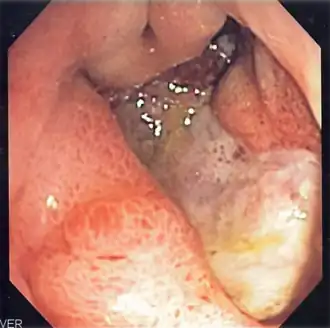

Úlcera péptica é uma lesão no revestimento do estômago, no duodeno ou, raramente, na parte final do esófago.[1][7] Uma úlcera no estômago denomina-se úlcera gástrica, enquanto que uma no duodeno se denomina úlcera duodenal. Os sintomas mais comuns são acordar de noite com dor na parte superior do abdómen ou dor na parte superior do abdómen que melhora ao comer. A dor é muitas vezes descrita como ardor ou dor ligeira constante. Entre outros possíveis sintomas estão a eructação, vómitos, perda de peso ou perda de apetite. Cerca de um terço das pessoas não manifesta sintomas.[1] Entre as possíveis complicações estão a hemorragia gastrointestinal, perfuração gastrointestinal e obstrução da saída gástrica. Cerca de 15% das pessoas apresentam hemorragia.[2]

As causas mais comuns são a bactéria Helicobacter pylori e os anti-inflamatórios não esteroides.[1] Entre as outras possíveis causas está o fumar, o stresse devido a doença grave, a doença de Behçet, a síndrome de Zollinger-Ellison, a doença de Crohn e a cirrose hepática.[1][3] As pessoas idosas são mais sensíveis aos efeitos dos anti-inflamatórios não esteroides. O diagnóstico pode ser suspeitado com base nos sintomas e confirmado com endoscopia ou ingestão de bário. A presença de H. pylori pode ser confirmada com análises ao sangue que detectam a presença de anticorpos, com um teste rápido da urease, com exames às fezes para observar sinais da bactéria ou com uma biópsia do estômago. Entre outras doenças que produzem sintomas semelhantes à úlcera péptica estão o cancro do estômago, a doença arterial coronária, a inflamação do revestimento do estômago ou cálculos na vesícula.[1]

A dieta não tem um papel significativo nem na causa nem na prevenção de úlceras.[8] O tratamento consiste em deixar de fumar, deixar de tomar anti-inflamatórios não esteroides, em deixar de ingerir bebidas alcoólicas e em medicamentos para diminuir a acidez do estômago. Os medicamentos usados são geralmente ou um inibidor da bomba de protões ou um antagonista do receptor H2 ao longo de quatro semanas recomendadas de tratamento inicial.[1] As úlceras causadas por H. pylori são tratadas com uma combinação de medicamentos como a amoxicilina, claritromicina e um inibidor da bomba de protões. Como a resistência antibiótica está a aumentar, o tratamento com antibióticos nem sempre é eficaz.[4] As úlceras hemorrágicas podem ser tratadas com cirurgia por endoscopia, sendo usada cirurgia aberta apenas nos casos em que a endoscopia não foi eficaz.[2]